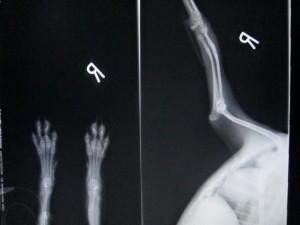

抜プレート後のレントゲンです。

骨折部位は少し太くなって治ります。